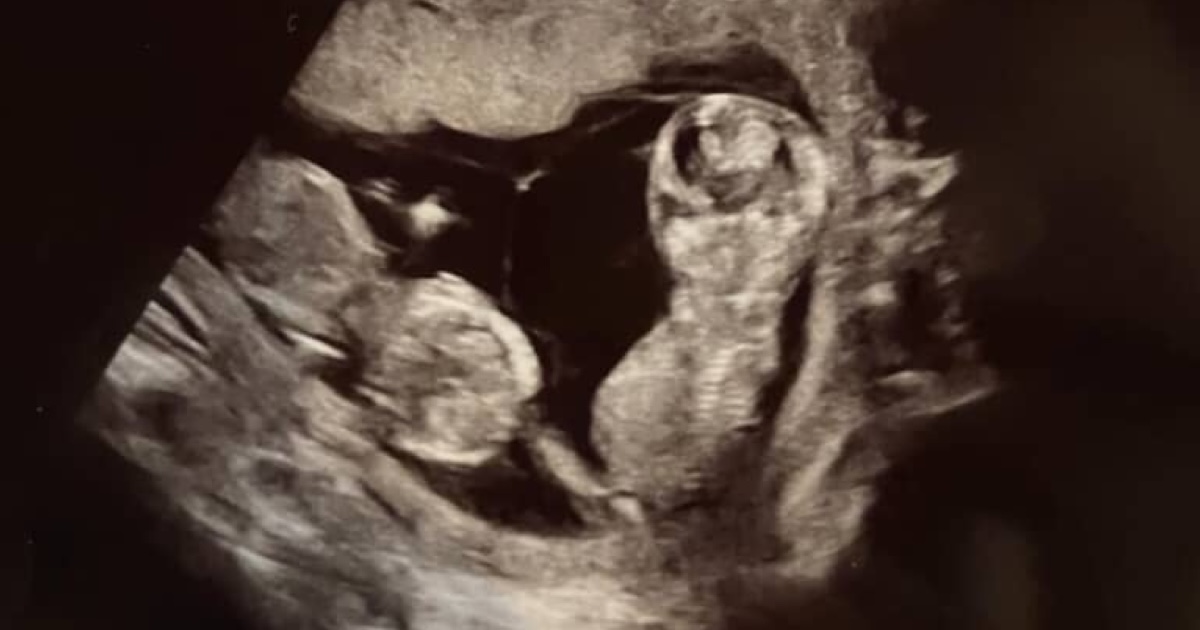

ママのお腹の中で寄り添う、双子の赤ちゃん→5年後……「うわぁ·····泣きそう」 姉妹の“現在の姿”に感動の声「たまらん」(1/2) | 育児 ねとらぼ

1年前や5年前……。少し前にインターネット上で話題になった投稿や動画を振り返って紹介する企画「昔のインターネット発掘!」。今回紹介するのは、2024年11月にThreadsで話題を呼んだ“双子の誕生前から現在までの成長を振り返るビフォーアフター投稿”です。投稿は記事執筆時点で約14万回表示され、1万件を超える“いい…